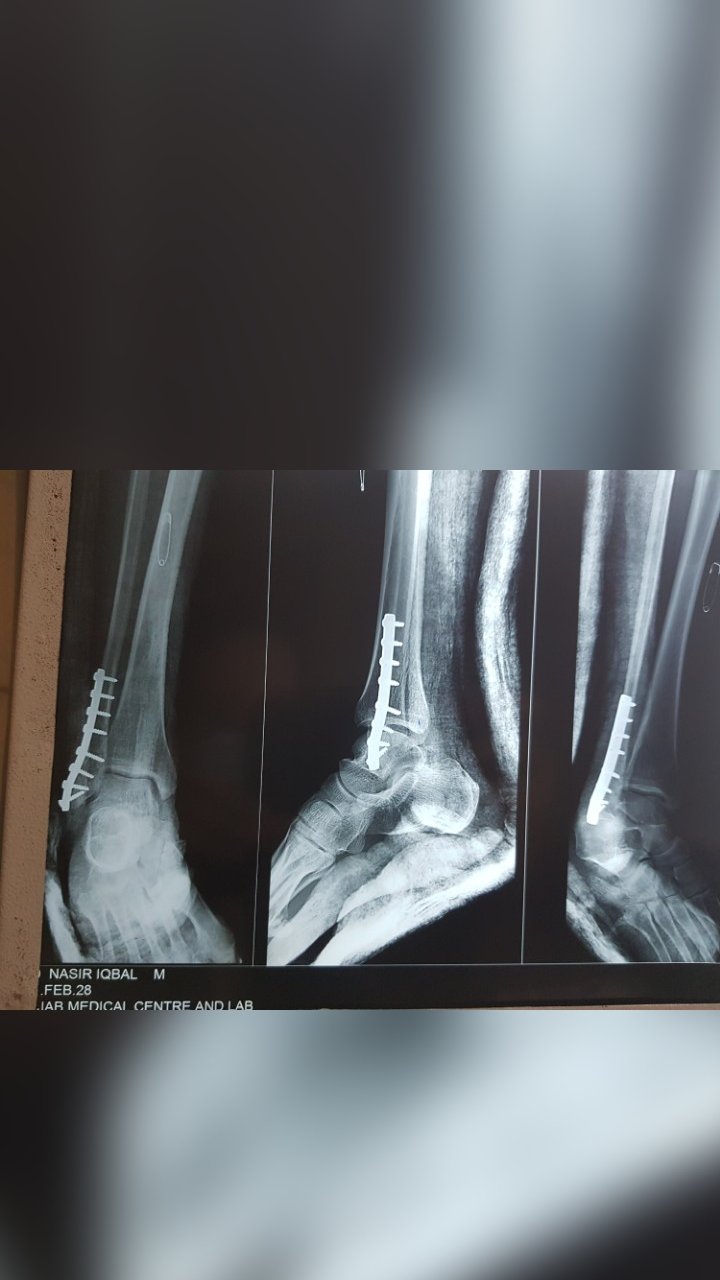

ANKLE FRACTURE SURGERY